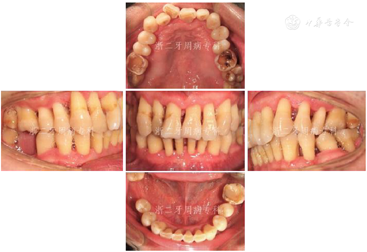

2008年9月:基础治疗完成后6个月牙周复诊,进行再评估,患者口腔卫生状况良好,牙龈炎症明显改善,PD≥7 mm的位点数从108个减少到4个,4~6 mm的位点数从61个减少到39个,平均探诊深度从7.0 mm降至3.0 mm,尤其是17远中2个位点,PD从12 mm分别降至3 mm(颊侧)与4 mm(舌侧);BOP(+)%从100%降到28.6%(图8)。各牙松动度较治疗前也明显改善,下前牙31、41仍有0.5 mm间隙。

针对深牙周袋、16、26、36、46釉质发育不全、牙列不齐、上前牙11扭转及46缺失,建议恢复16、26、36、46咬合面正常形态、牙周手术治疗、正畸及修复46,但患者暂时不考虑牙周手术、正畸和修复治疗。因此,仅进行牙周维护及11~13、21~23松动牙超级粘结剂牙周固定。

2009年4月:牙周基础治疗后1年复诊。患者口腔卫生可,牙龈色粉质韧,仅下前牙舌侧可见少量软垢,局部龈缘充血(图9),并惊喜地发现:下前牙31、41间隙已完全关闭。牙齿松动度、PD、BOP(+)%与半年前无明显变化(图10)。全口曲面体层X片示:牙槽嵴顶硬骨板较2007年12月清晰,14、17、24、34、36局部有牙槽骨修复、36根尖周骨密度增加,其余位点牙槽骨均未见进一步吸收;46缺牙区牙槽骨密度和高度增加(图11),提示牙周基础治疗后牙周状况得到了明显改善。因37、46缺失牙未及时修复,16略伸长,38近中倾斜,再次建议患者正畸治疗,直立38、压入16,排齐整平牙列,修复缺失牙37、46。患者拒绝正畸和修复治疗。予以16调磨、牙周维护治疗、35~44超级粘结剂牙周固定。